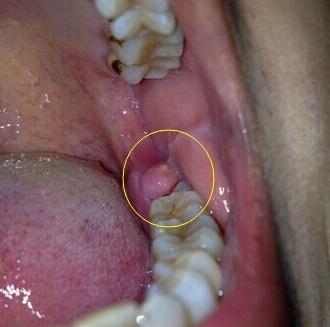

临床上智齿在萌出过程中形成与口腔相通的盲袋,盲袋内易储存食物残渣

一, 智齿冠周炎:各种类型的萌出不全让智齿被龈瓣覆盖,形成盲袋容易藏

智齿没有完全萌出的话会形成一个盲袋,这个盲袋是引起感染的细菌的

a处为智齿,b处为牙冠与牙龈形成的盲袋丨wikipedia